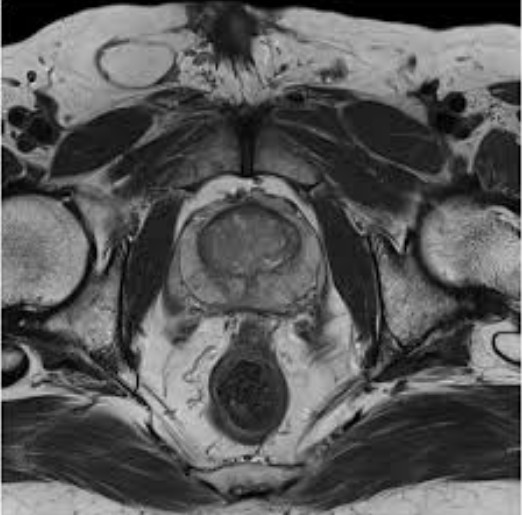

МРТ органов малого тазаМРТ малого таза позволяет визуализировать все органы и ткани, входящие в данную анатомическую группу: прямую кишку, мочевой пузырь, жировую клетчатку, лимфоузлы, костные элементы, а также матку, маточные трубы, влагалище и яичники у женщин, у мужчин – семенные пузырьки и предстательную железу. Из-за тесного расположения этих органов патологические нарушения, которые происходят в одной структуре, воздействуют на функциональное состояние близлежащих органов.

В ходе сканирования получают серию тонких срезов данной области, которые визуализируются как черно-белые снимки. Врач кабинета МРТ в процессе расшифровки оценивает взаимное расположение органов и тканей, их однородность, плотность, контрастность, форму и очерченность границ. Также в заключении специалист отмечает наличие инородных тел, патологических образований, расширенность мочеточников и другие параметры.